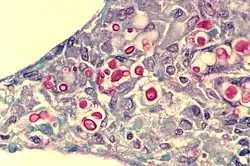

Cryptococcus neoformans typically grows as a yeast (unicellular) and replicates by budding. It makes hyphae during mating, and eventually creates basidiospores at the end of the hyphae before producing spores. Under host-relevant conditions, including low glucose, serum, 5% carbon dioxide, and low iron, among others, the cells produce a characteristic polysaccharide capsule.[8] The recognition of C. neoformans in Gram-stained smears of purulent exudates may be hampered by the presence of the large gelatinous capsule which apparently prevents definitive staining of the yeast-like cells. In such stained preparations, it may appear either as round cells with Gram-positive granular inclusions impressed upon a pale lavender cytoplasmic background or as Gram-negative lipoid bodies.[9] When grown as a yeast, C. neoformans has a prominent capsule composed mostly of polysaccharides. Under the microscope, the India ink stain is used for easy visualization of the capsule in cerebral spinal fluid.[10] The particles of ink pigment do not enter the capsule that surrounds the spherical yeast cell, resulting in a zone of clearance or "halo" around the cells. This allows for quick and easy identification of C. neoformans. Unusual morphological forms are rarely seen.[11] For identification in tissue, mucicarmine stain provides specific staining of polysaccharide cell wall in C. neoformans. Cryptococcal antigen from cerebrospinal fluid is thought to be the best test for diagnosis of cryptococcal meningitis in terms of sensitivity, though it might be unreliable in HIV-positive patients.[12]

In human infection, C. neoformans is spread by inhalation of aerosolized basidiospores or dehydrated fungal cells, and can disseminate to the central nervous system, where it can cause meningoencephalitis.[22] In the lungs, C. neoformans cells are phagocytosed by alveolar macrophages.[23] Macrophages produce oxidative and nitrosative agents, creating a hostile environment, to kill invading pathogens.[24] However, some C. neoformans cells can survive intracellularly in macrophages because of the protective nature of the polysaccharide capsule as well as its ability to produce melanin.[23][3] Intracellular survival appears to be one of the factors contributing to latency, disseminated disease, and resistance to eradication by antifungal agents. One mechanism by which C. neoformans survives the hostile intracellular environment of the macrophage involves upregulation of expression of genes involved in responses to oxidative stress.[23]

Infection begins in the lungs, and from there the fungus can disseminate to the brain and other body parts via macrophages. An infection of the brain caused by C. neoformans is referred to as cryptococcal meningitis, which is most often fatal when left untreated.[5][31] Cryptococcal meningitis causes more than 180,000 deaths annually.[32] CNS (central nervous system) infections may also be present as a brain abscesses known as cryptococcomas, subdural effusions, dementia, isolated cranial nerve lesions, spinal cord lesions, and ischemic stroke. The estimated one-year mortality of HIV-related people who receive treatment for cryptococcal meningitis is 70% in low-income countries versus 20–30% for high-income countries.[33] Symptoms include headache, fever, neck stiffness, nausea and vomiting, photophobia. Diagnosis methods include a serum cryptococcal antigen test and lumbar puncture with cerebrospinal fluid (CSF) examination to detect C. neoformans.[34]